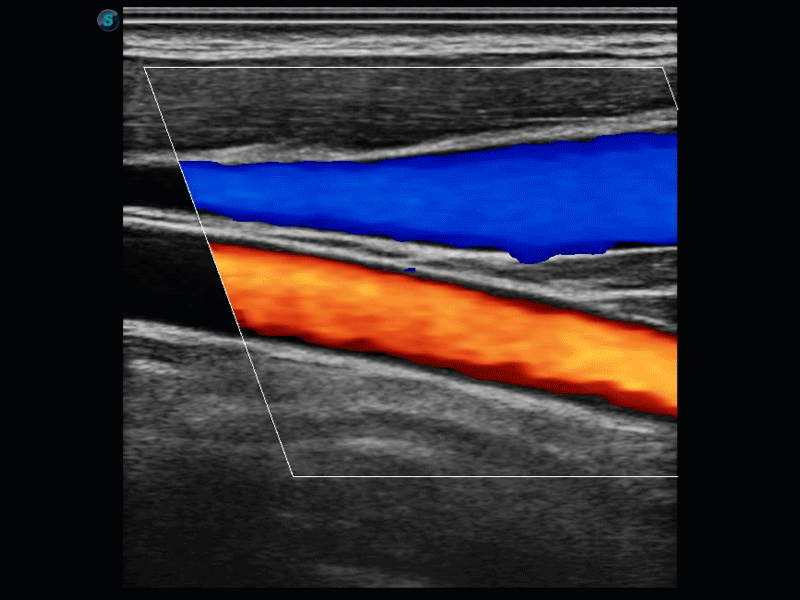

凭借狗万官方网站先进的成像技术和优异的探头技术提供的清晰的图像表现,您可以更自信地做出临床决策。

复合材料线阵探头